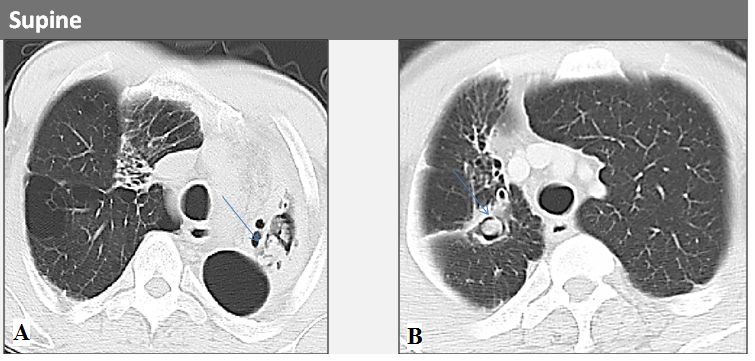

3、CT表现:管状或囊状手指区域支气管分布增加不透明度,表示支气管扩张内粘液堵塞,主要累及上叶(图8、9)。

图8:胸部X线片显示由于ABPA中的支气管粘液堵塞导致左下叶中的管状阴影。

图9:高分辨率CT显示由于支气管扩张伴粘液嵌塞,导致的下叶中的支气管周围增厚和明显的结节影。